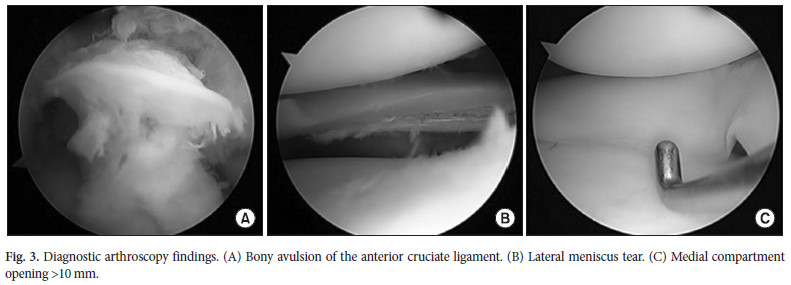

L’arthroscopie a permis de diagnostiquer l’avulsion fémorale du LCA (figure 3A), la lésion inférieure de la corne postérieur du ML (Fig. 3B) et une ouverture> 10 mm du compartiment médial suggérant atteinte du LCM (Fig. 3C).

L’arthroscopie a permis de diagnostiquer l’avulsion fémorale du LCA (figure 3A), la lésion inférieure de la corne postérieur du ML (Fig. 3B) et une ouverture> 10 mm du compartiment médial suggérant atteinte du LCM (Fig. 3C).